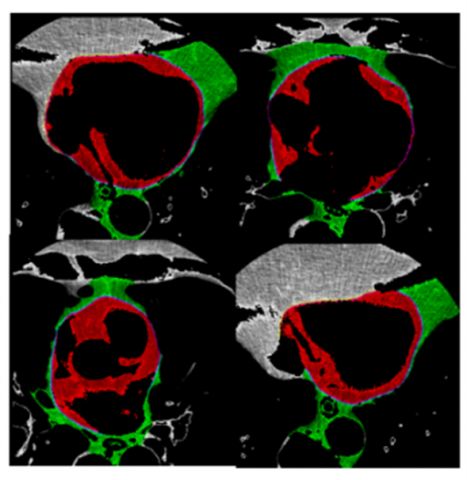

The performance of the modified FPN-based model is compared with existing models in terms of the Dice similarity coefficient (DSC), Jaccard similarity coefficient (JSC), and Hausdorff distance (HD). The validity and repeatability of the proposed method were evaluated through 10-fold cross-validation experiments on an input dataset. Each fold involved splitting the dataset into seventy percent for training and thirty percent for validation. The model output is shown in Figure 6(a). The red color denotes the epicardial fat segmentation and the green color denotes the mediastinal fat segmentation outputs. It is observed that the Modified FPN model successfully identifies and differentiates between the epicardial and pericardial fat depots.

(a)

(b)

Figure 6. (a) Segmentation results; (b) loss analysis